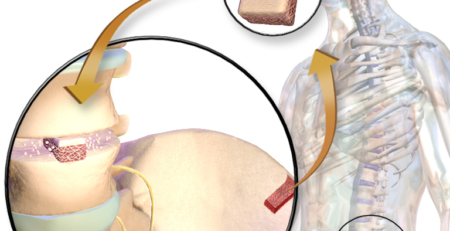

2. العلاج الجراحي (إعادة بناء الرباط الصليبي):

يُوصى بالعلاج الجراحي واجراء عملية الرباط الصليبي عند حدوث قطع كامل في الرباط الصليبي، خاصة لدى الرياضيين.

تُجرى العملية باستخدام تقنيات المنظار الحديثة التي تقلل الألم وفترة التعافي.

يُجري الدكتور هشام عبد الباقي عملية الرباط الصليبي بالمنظار مستخدمًا أحدث الأدوات الجراحية مع تطبيق بروتوكولات عالمية لضمان أفضل النتائج واستعادة الأداء الوظيفي للركبة بأمان.